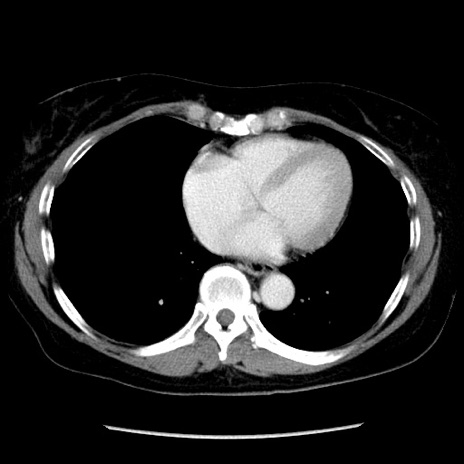

症例6(横断像)

【症例】50歳代女性

【主訴】下腹部痛

【現病歴】本日朝より下痢2回あり。 昼食を食べた後、嘔吐3回、下腹部痛認め、症状軽快せず、当院救急搬送。

最終食事:本日昼(生ものなし)。 昨日の夜、刺身を食ぺたとのこと。周囲に同様の症状の者なし。普段、排便は毎日あるとのこと。

【既往歴】卵巣癌術後(8年前に当院で卵巣摘出)

【身体所見】 意識清明、腹部:平坦、腸蠕動音→、やや硬、下腹部自発痛・圧痛あり、反跳痛あり、筋性防御なし。

【データ】WBC 16000、CRP 0.01